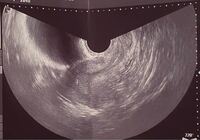

5週 胎嚢 見えない hcg高い- 妊娠5週5日(週数ほぼ正確)胎嚢確認日。 hcg 1434 だが、胎嚢確認できず。 胎嚢が見えない原因、3つの可能性 胎嚢まだが発育してなくて見えていない状態; 胎嚢が見えるには通常1000くらいの値が必要らしい。 やっぱり低いHcg。 5週目で普通は胎嚢確認できるらしいが できてないのはおかしいと焦る先生。 (排卵日のズレで見えない

正常妊娠では、着床開始後まもなくhCGが検出され始め、妊娠4週0日で血中hCG値は100~0 IU/lとなり、5週0日には約00~4000 IU/lと指数関数的に増加する。 00 IU/l以上のhCG分泌があ 23/1/25 1023 0 回答 性交日と数週が合いません。 生理開始日が12月10日なので単純計算だと今日1月25日で6週4日だと思っていたのですが、本日産婦人科で診てもらうと胎嚢し